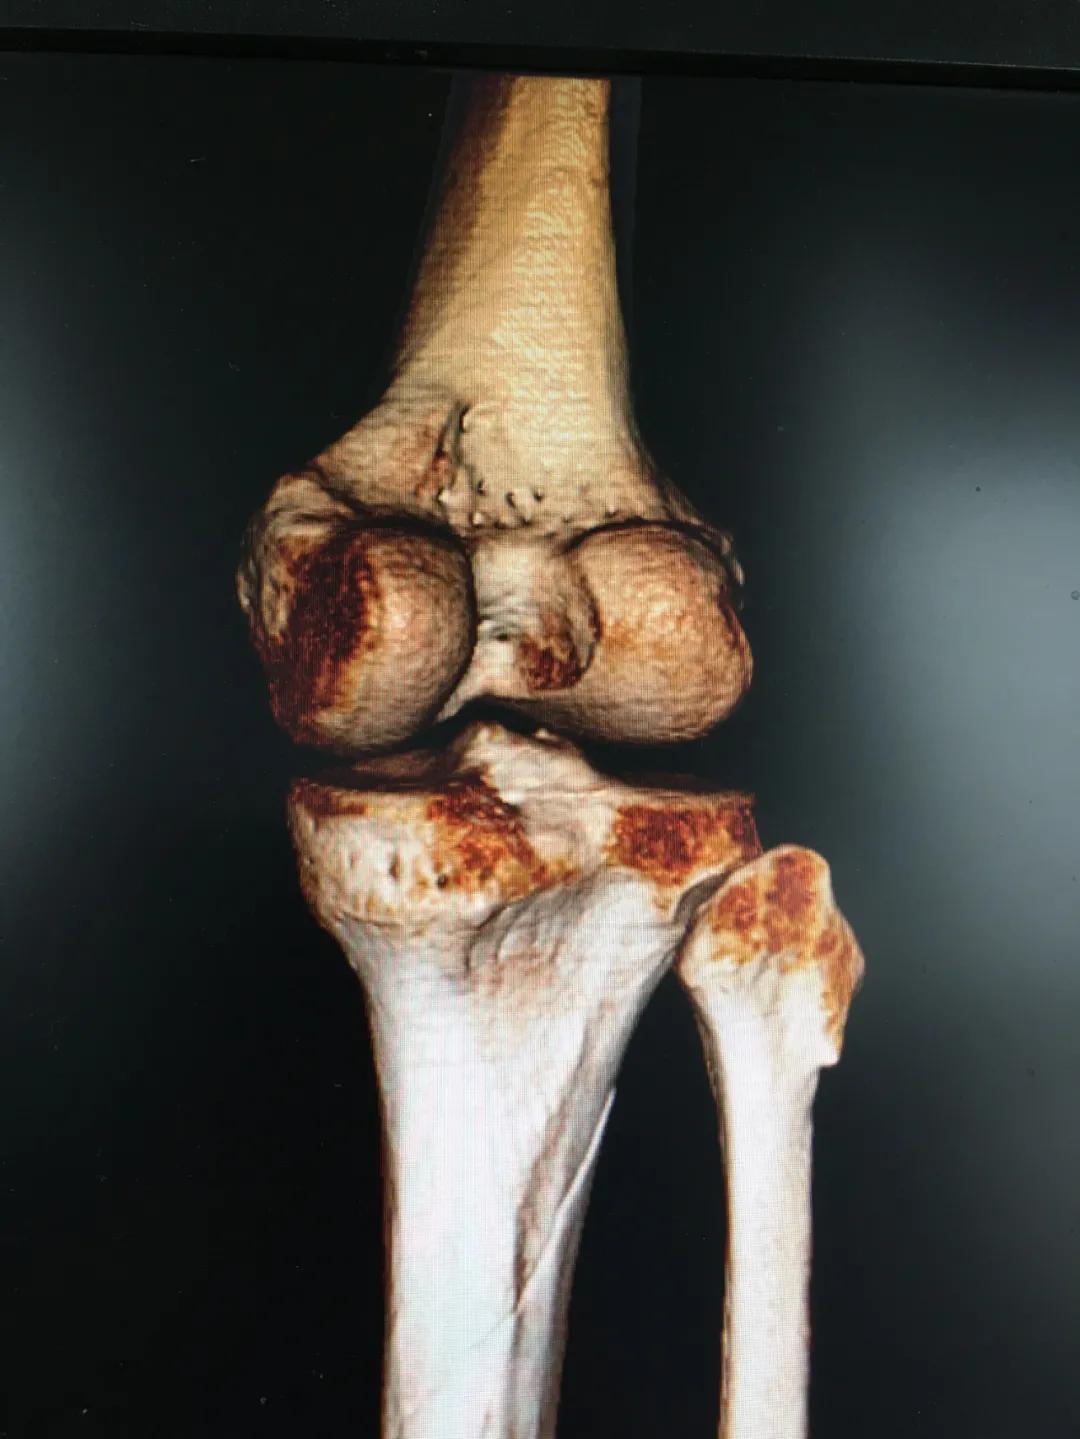

刘阿姨半个月前骑电动车时与小轿车相撞,导致了左胫腓骨粉碎性骨折,小腿骨碎成了三段。"然而,在术前丈夫周先生对刘阿姨的治疗却拿不定主意。“我妻子身上有多种基础疾病,患高血压15年,糖尿病也有8年多了。这里的诊疗技术,能不能保障手术的安全?手术前,我们家属的心中确实也很忐忑!"由于对我院创伤技术水平不太了解,周先生已经准备要转院治疗。

为患者实施的骨折微创复位固定技术是创伤骨科的特色技术。相较传统手术需要20公分的切口,微创手术只需要3公分左右。闭合复位髓内钉固定技术、经皮插板内固定技术(mippo技术)、闭合复位空心螺钉固定技术等一系列的微创复位固定技术,具有切口小、出血少、创伤小、愈合快、疤痕小等优点,骨折术后并发症明显降低,患者还可以早期负重功能锻炼。

另一位患者朱先生因车祸导致了右胫腓骨骨折,同样的小腿三段骨折,实施了微创闭合复位髓内钉固定术后,目前已经逐步进行康复功能锻炼。